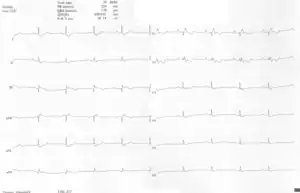

- A 10-lead ECG of a woman with Ebstein's anomaly: The ECG shows signs of right atrial enlargement, best seen in V1. Other P waves are broad and tall, these are termed "Himalayan" P waves. Also, a right bundle-branch block pattern and a first-degree atrioventricular block (prolonged PR-interval) due to intra-atrial conduction delay are seen. No evidence of a Kent-bundle is seen in this patient. The T wave inversion in V1-4 and a marked Q wave in III occur; these changes are characteristic for Ebstein's anomaly and do not reflect ischemic ECG changes in this patient.